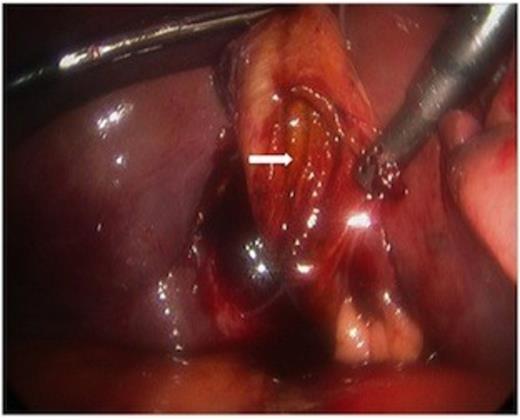

While hepatic contrast extravasation in a stable patient is typically treated with angioembolization, proximity to the gallbladder was concerning for gallbladder injury. Exploratory laparoscopy was performed and the gallbladder was found to be perforated and nearly completely avulsed from the liver (Figures 2 and 3).

At laparoscopy, the gallbladder (large white arrow) was found partially avulsed from the gallbladder fossa (small white arrow).